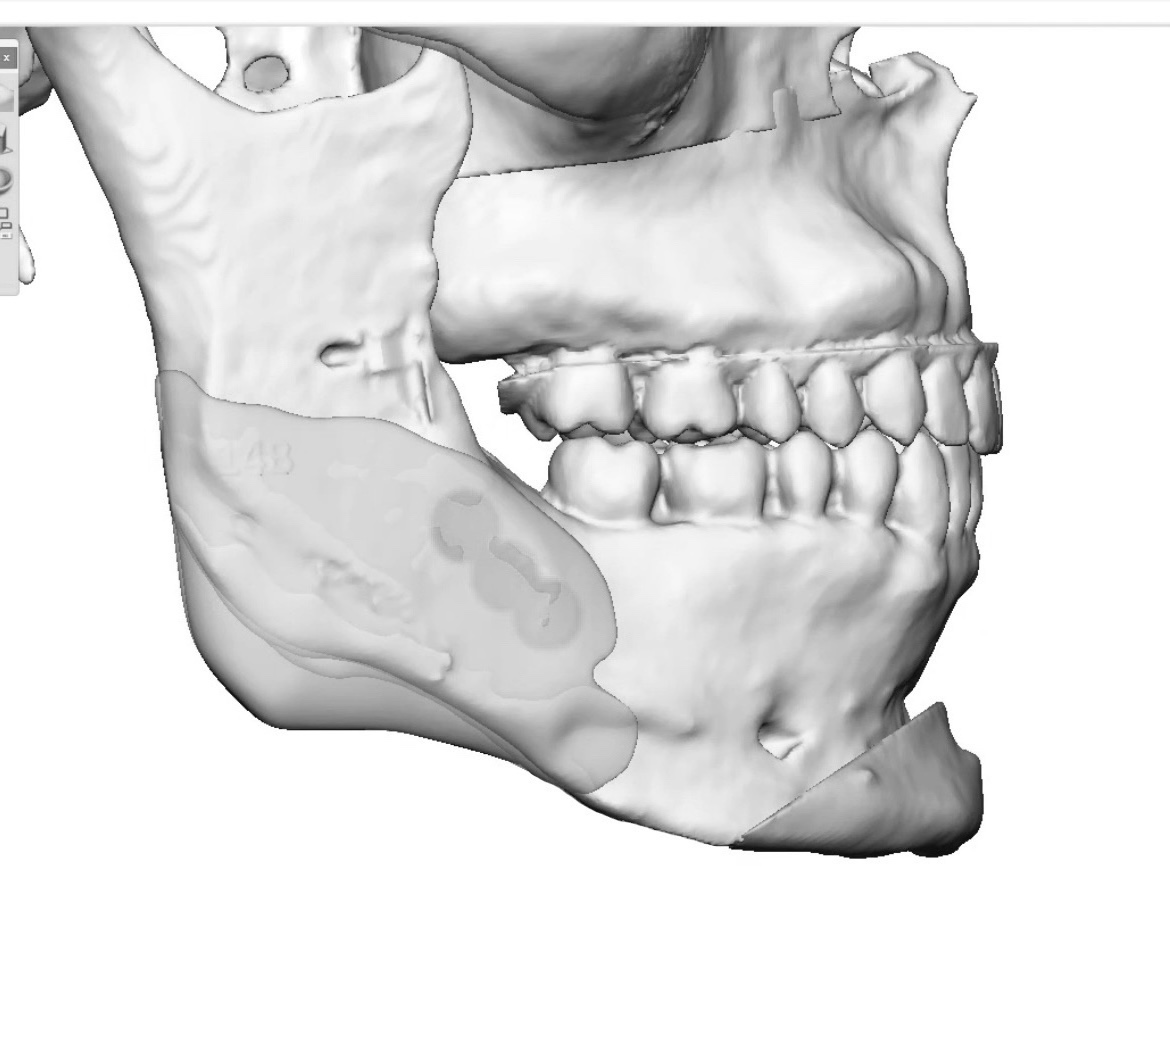

Getting a Le fort 1 with sliding genio to shorten my long face, replacing my jaw implants and adding cheek implants. Doing 6mm impaction with 4mm advancement. No BSSO. What do you guys think of the implant design? Angle too low? Attached pics are before and after